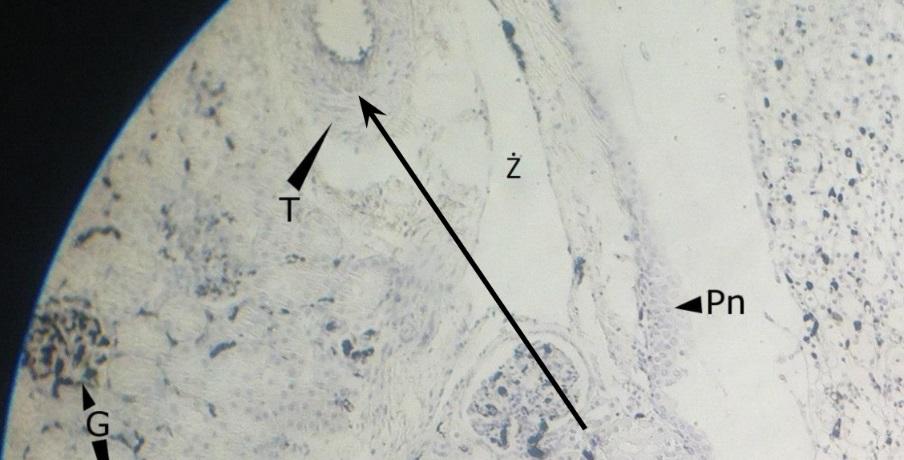

Pytanie 303

tętniczki doprowadzające i odprowadzające (nerka, barwienie tuszem chińskim)

Pytanie 304

naczynie odżywcze (nerka, barwienie tuszem chińskim)

Pytanie 305

naczynia międzypłacikowe (nerka, barwienie tuszem chińskim)